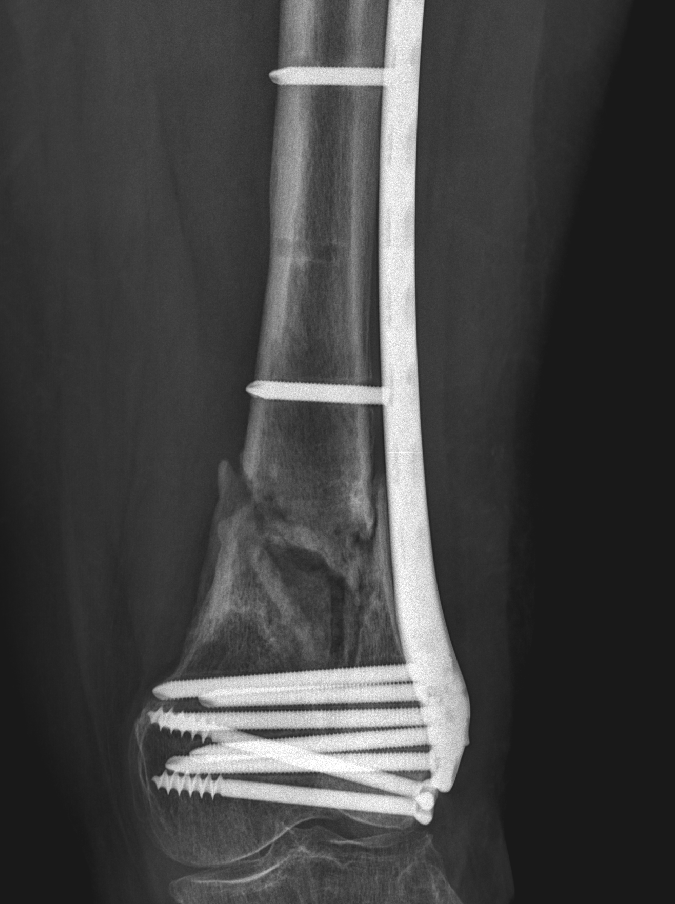

@traumaticum Short working length of plate, too many distal screws will add to destruct vascularity of the already poor biology

why did this go onto non union?

60yo F, moderate energy trauma. Methotrexate and Secukinumab. Index LISS OP 10m ago